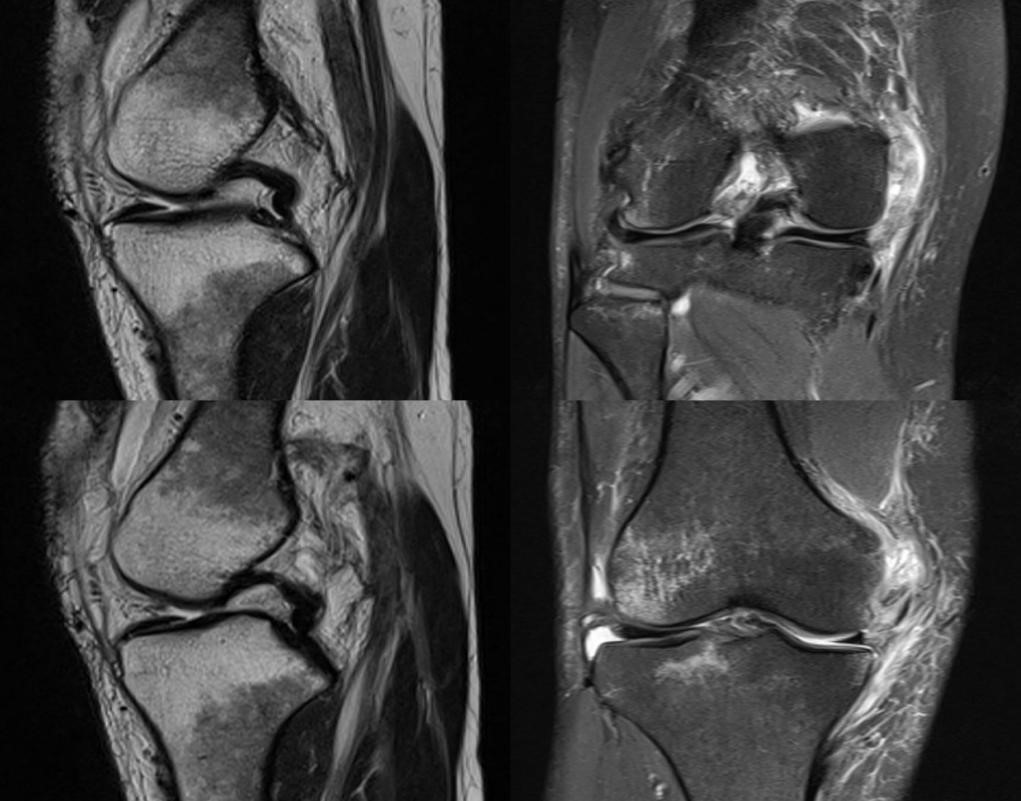

急性前交叉韧带损伤发生时,患者常可听到撕裂声或感到关节异常,随后伴有膝关节剧烈疼痛、活动受限与肿胀。Lachman试验、轴移试验和前抽屉试验这三项检查的敏感度和特异度最佳。MRI是评估前交叉韧带损伤的主要影像学方法。MRI可评估膝关节有无合并半月板损伤、软骨及其他韧带损伤,在急性损伤期用于观察对吻型骨挫伤与骨髓水肿信号等。X线主要用于排除是否合并骨折。